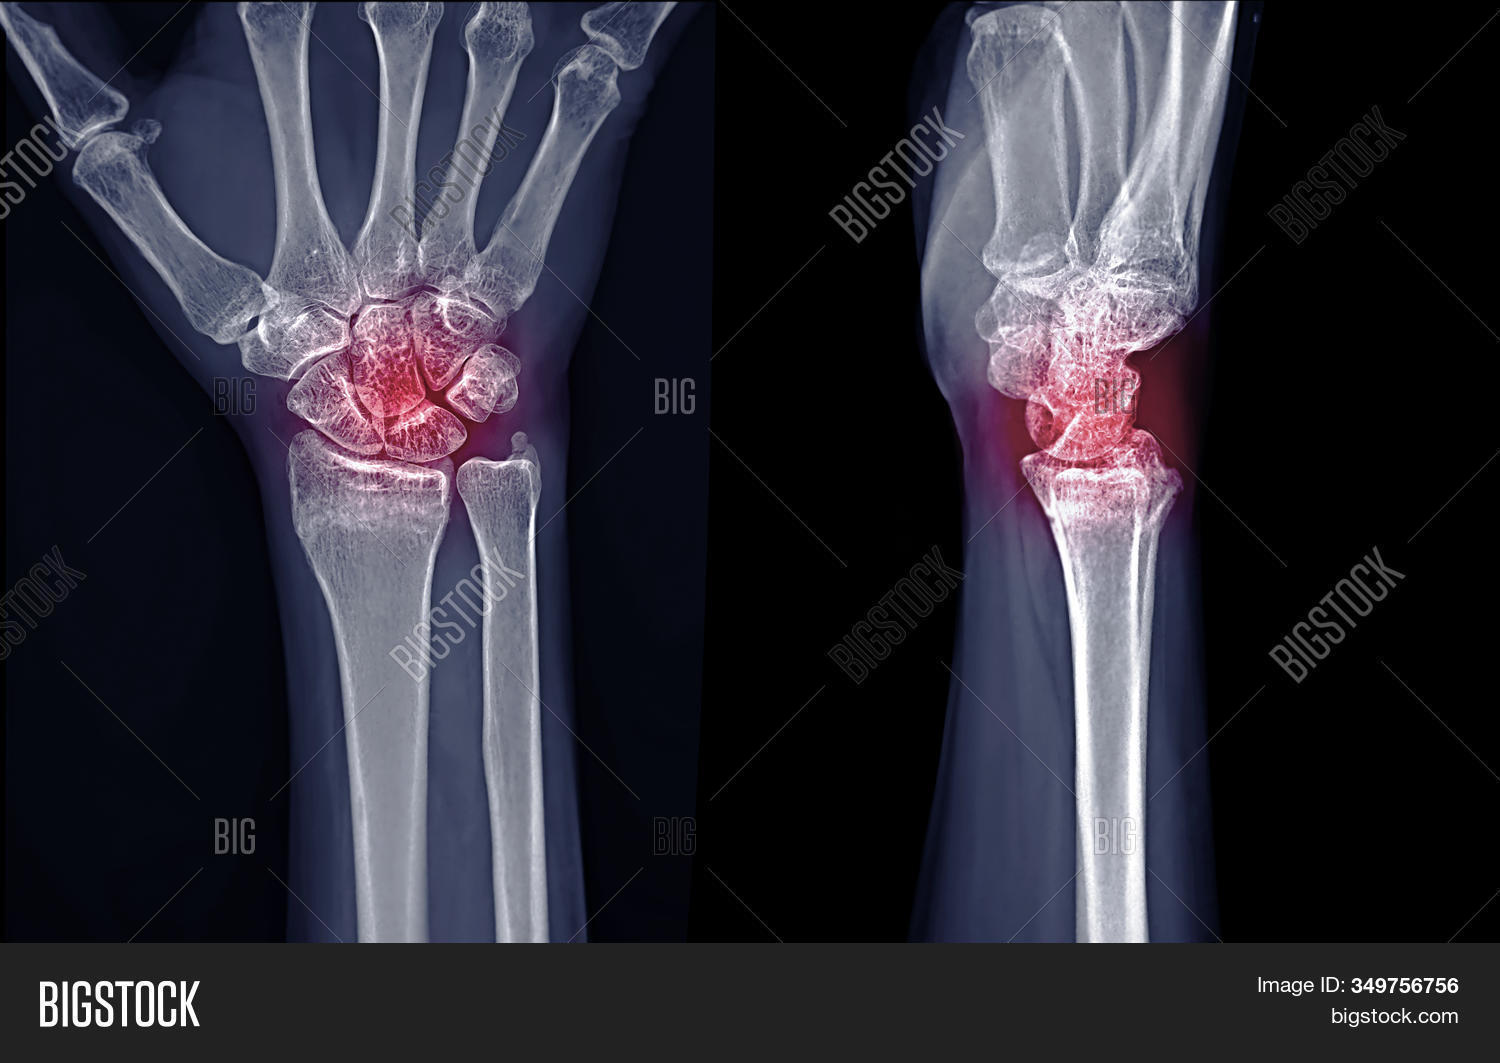

Xray Image Right Image & Photo (Free Trial) Bigstock Right Wrist Xr The image displays the inner structure (anatomy) of your wrist in black and white. A recommended systematic checklist for reviewing musculoskeletal exams is soft tissue areas, cortical margins, trabecular patterns, bony alignment, joint. 1 article features images from this case. This article provides a comprehensive approach to wrist radiographs, including techniques and common indications for imaging. 22 public playlists include. Right Wrist Xr.

Xray image of Right wrist joint Ap and Lateral view for diagnosis Right Wrist Xr This article provides a comprehensive approach to wrist radiographs, including techniques and common indications for imaging. The image displays the inner structure (anatomy) of your wrist in black and white. The scaphoid bone is the most commonly fractured wrist bone. In this case 2 extra views are added to the standard views (oblique, and pa with ulnar deviation). 22 public. Right Wrist Xr.